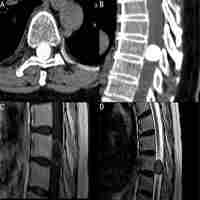

| Abstract | BackgroundThe progesterone receptor (PR) is variably expressed in most meningiomas and was found to have prognostic significance. However, the correlation with patient age, tumor location, time to recurrence, and pattern of regrowth has scarcely been discussed.MethodsA surgical series of 300 patients with meningiomas is reviewed. The PR expression was classified as: 0. absent; 1. low (<15%); 2. moderately low (16–50%); 3. moderately high (51–79%); 4. high (≥80%). The PR values were correlated with the patient age and sex, meningioma location, WHO grade, Ki-67 MIB1, recurrence rate, pattern of recurrence (local-peripheral versus multicentric diffuse), and time to recurrence.ResultsThe PR expression has shown lower rate of high expression in the elderly group (p = 0.032) and no sex difference (including premenopausal versus postmenopausal women), higher expression in medial skull base and spinal versus other locations (p = 0.0036), inverse correlation with WHO grade and Ki67-MIB1 (p < 0.0001). Meningiomas which recurred showed at initial surgery higher rates of low or moderately low PR expression than the non-recurrent ones (p = 0.0004), whereas the pattern of regrowth was not significant. Higher rates of PR values ≥80% were found in cases with time to recurrence >5 years (p = 0.036).ConclusionThe higher PR expression in medial skull base meningiomas, the significant correlation with the time to recurrence, the lack of difference of PR expression between premenopausal and po... |